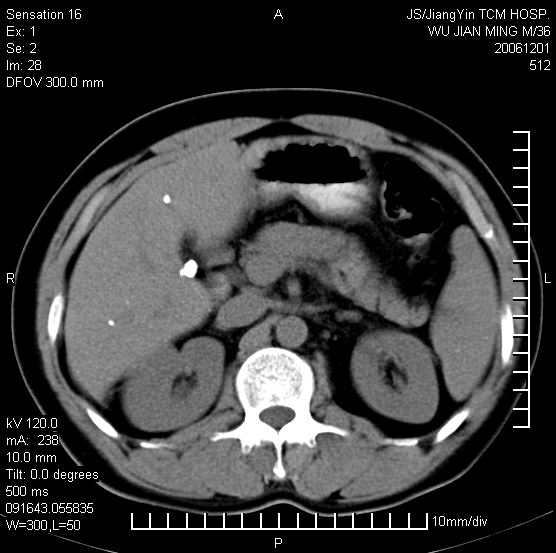

以下是引用dyqct在2006-12-1 21:17:00的发言:[br]左心缘旁及后肋膈窦区见巨大椭圆形混杂密度肿块,周围见大小不等斑片状钙化,内部无强化,周围包膜轻度强化,心脏明显受压变形,即明显占位效应,肿块广基与心包、膈相连。肝、脾内、肝门见多数小结节状钙化影。[br]考虑:1、左心缘旁及后肋膈窦区慢性包裹性胸膜炎(结核性);[br] 2、肝、脾及肝门淋巴结核已钙化。[br]

以下是引用zrs在2006-12-2 17:28:00的发言:[br]肺内、肝脾内虽有钙化,但不支持结核性胸胸膜炎包裹,而支持寄生虫感染![br][br]

以下是引用zyx168在2006-12-2 10:10:00的发言:[br][br]肝脾肺内多发钙化灶